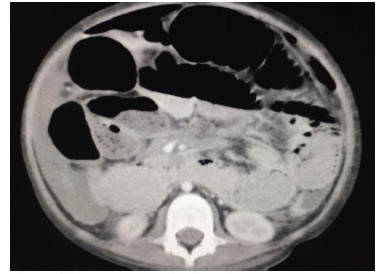

Presentó un cuadro clínico de dolor abdominal, obstrucción intestinal y ascitis de un mes evolución; además, síndrome de respuesta inflamatoria sistémica que produjo taquicardia y fiebre. Se requirió su hospitalización y la práctica de una laparotomía de urgencia. En la ecografía abdominal total se encontró líquido libre en la cavidad abdominal y, la tomografía computadorizada de abdomen contrastada con medio hidrosoluble, un neumoperitoneo masivo (figura 2).

Para el diagnóstico imaginológico, se puede emplear la ecografía abdominal total, la cual permite detectar líquido libre con tabiques finos y linfadenopatías con centro hipoecogénico, que corresponde a necrosis de caseificación. En la tomografía computadorizada de abdomen se aprecia engrosamiento de las asas, especialmente el íleon y la válvula ileocecal, con nódulos en el mesenterio, líquido libre, signos de obstrucción intestinal y perforación 17,18,19.

En la ecografía de este paciente se encontró líquido libre, escaso pero sin tabiques y no se evidenciaron adenomegalias, mientras que en la tomografía se observaron signos de obstrucción intestinal con perforación 20, 21. La colonoscopia se puede emplear con el fin de detectar lesiones en la válvula ileocecal y en el íleon distal; sin embargo, los hallazgos pueden ser similares a los de la enfermedad de Crohn, como lo reportan Wu, et al. En la esofagogastroduodenoscopia no se demostraron ulceraciones sugestivas de tuberculosis22,23,24.